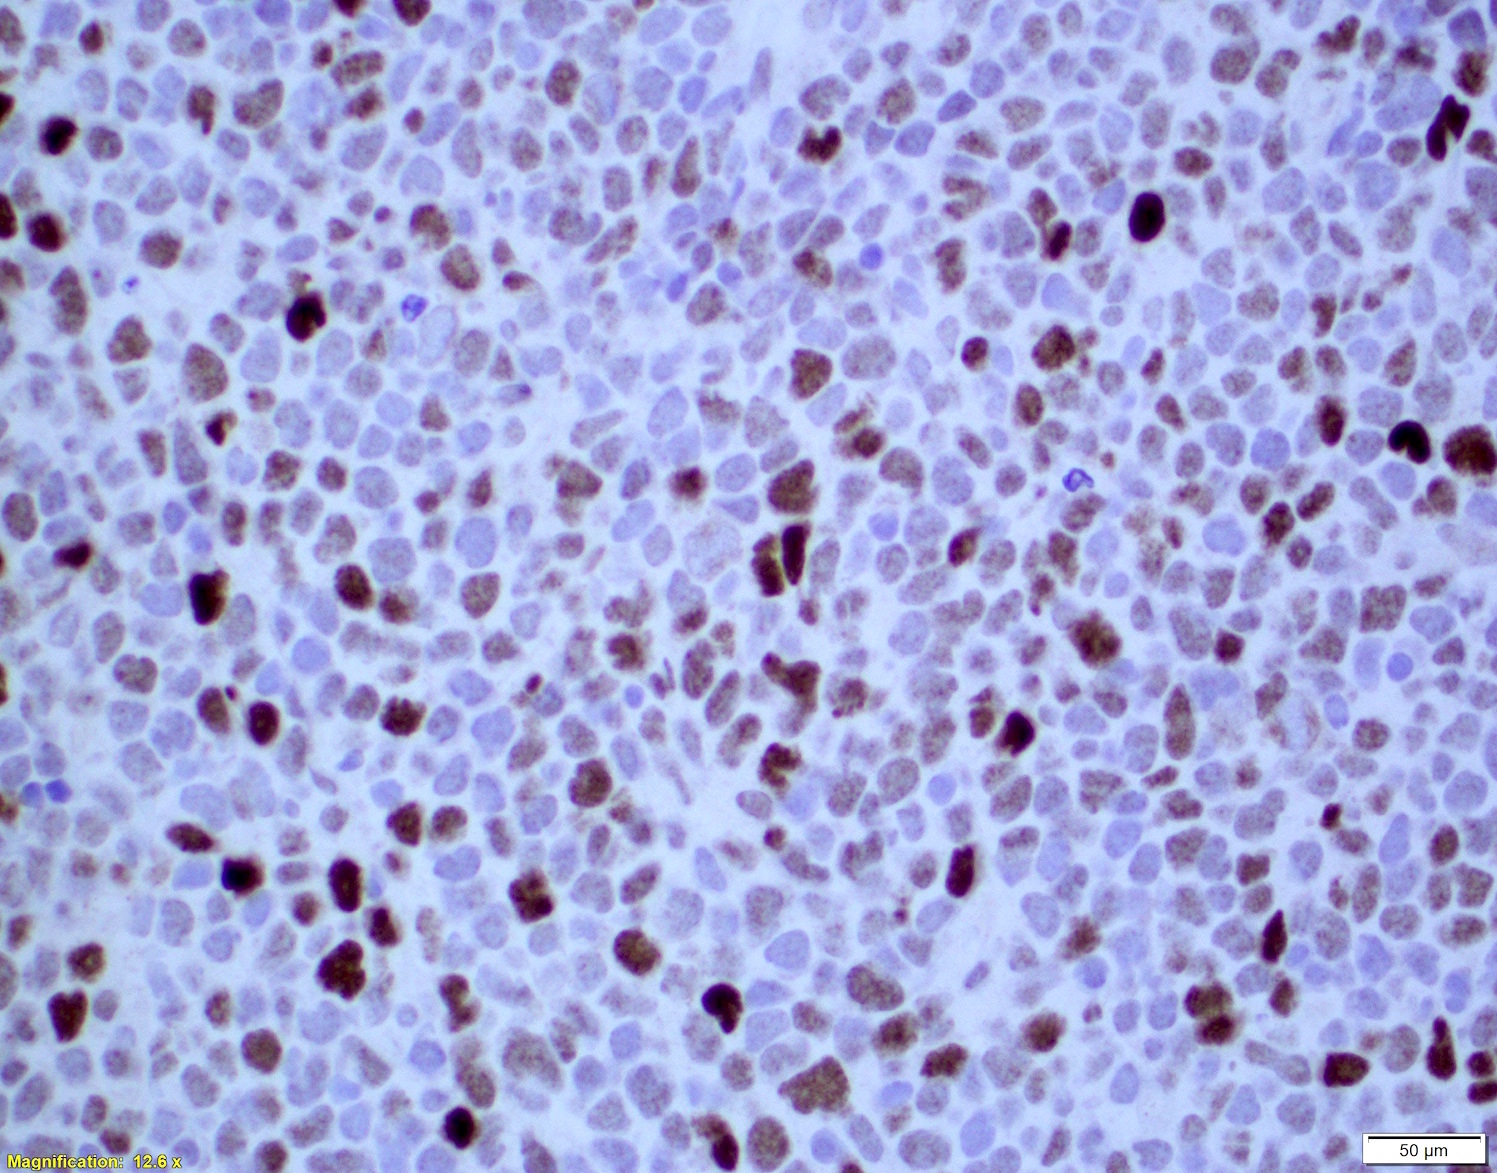

Microscopic (histologic) images

- Ki67 count (J Hematop 2009;2:103)

- Note: Ki67 index is not sufficient to classify as blastoid or pleomorphic subtype

- Classical mantle cell lymphoma might also show high cell proliferation (Blood 2008;111:2385)